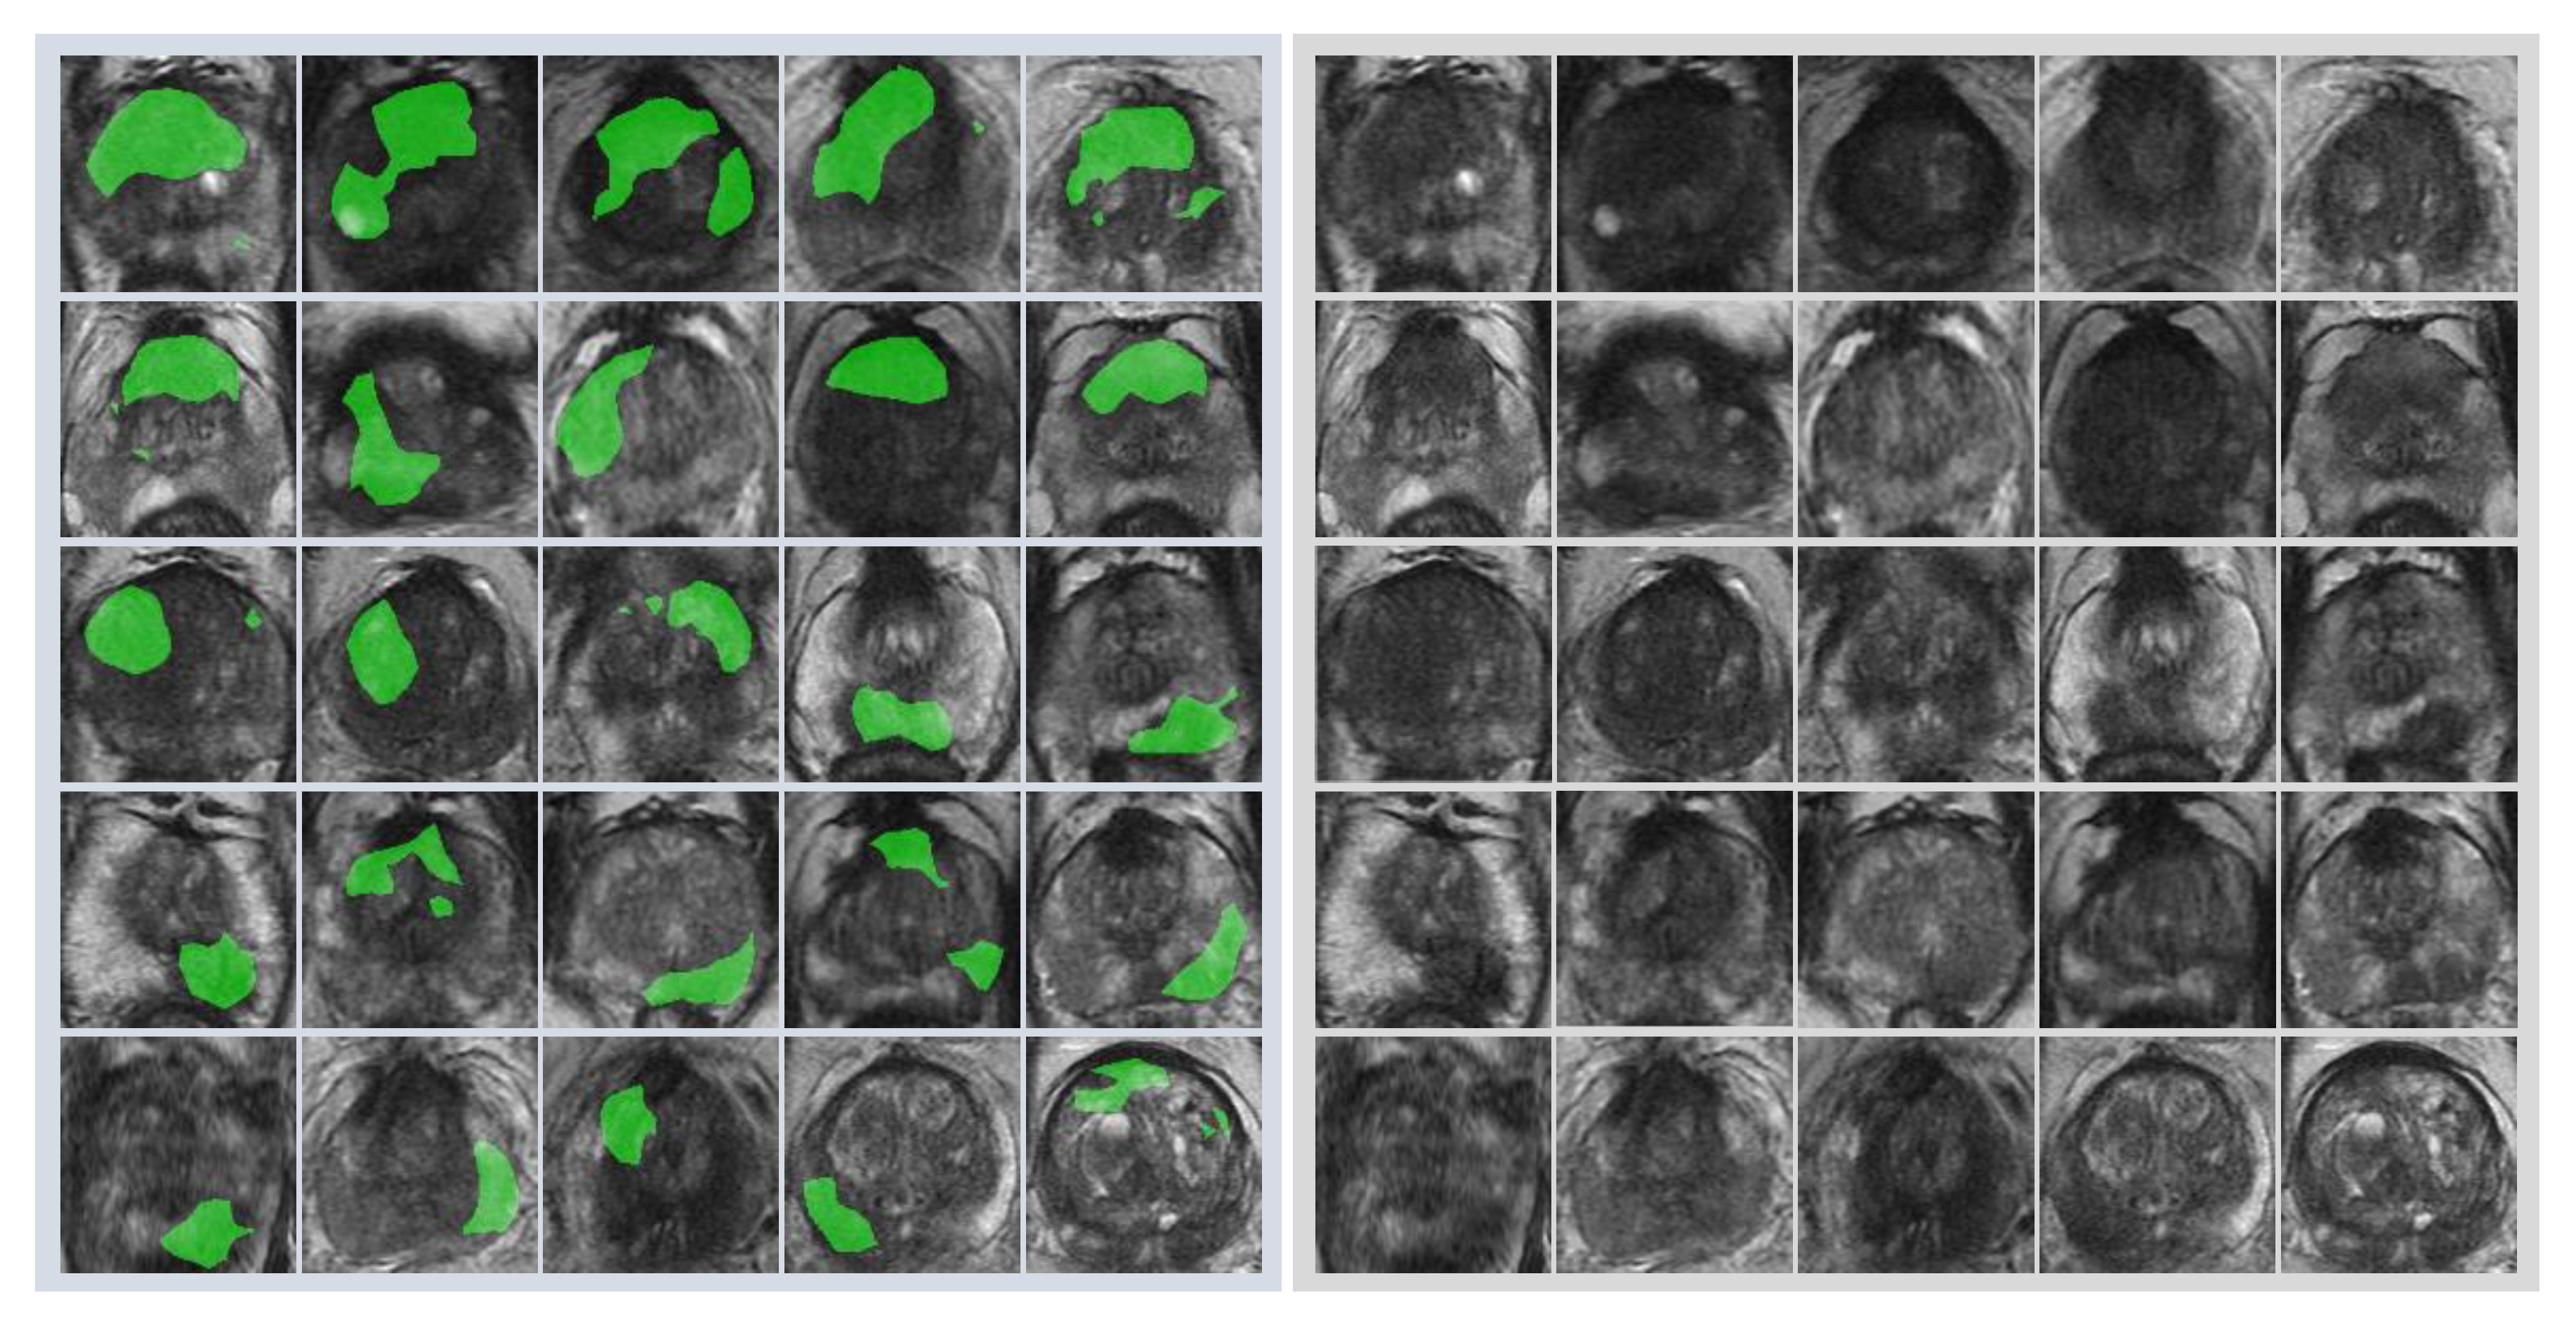

First, radiologists evaluated multiparametric MR images that corresponded to the T2-weighted MR images analyzed by deep learning algorithms based on PI-RADS. We locationally compared the deep learning-focused regions of the MR images with the radiologist-identified targets (PI-RADS category ≥ 4). We found that the deep learning-focused regions overlapped the radiologist-identified targets in 70.5% of the MR images (p < 0.001). Next, the locational correlation between the deep learning-focused regions in the MR images and genuine cancer locations based on 3D reconstruction of pathological images was evaluated. We found that the deep learning-focused regions overlapped genuine cancer locations in 72.1% of the MR images (p < 0.001). In the remaining MR images, deep learning focused the following regions: transition zone (10.1%), peripheral zone (7.8%), and the others (region outside of prostate gland). Figure 4 and Supplementary Table S1 show four representative cases of the comparative analyses. In cases one and two, deep learning focused on correct cancer regions. On the other hand, in case three, deep learning focused on a non-cancerous region. In case four, deep learning focused on normal adipose tissue. Figure 5 shows 25 representative images with overlapping areas between deep learning-focused regions and genuine cancer locations. The overlapped areas are colored in green. Finally, pathologists evaluated the deep leaning-focused regions in the non-overlapping images and found that deep learning focused on following regions: dilated prostatic ducts, lymphocyte aggregation, and others (normal stroma and adipose tissue) (Supplementary Figure S3).

Figure 5.

Representative images with overlapping areas between deep learning-focused regions and genuine cancer locations. Left image group: 25 images with overlapping areas between deep learning-focused regions and genuine cancer locations. The overlapped areas are colored in green. Right image group: corresponding 25 raw MR images. MR images = Magnetic resonance images.